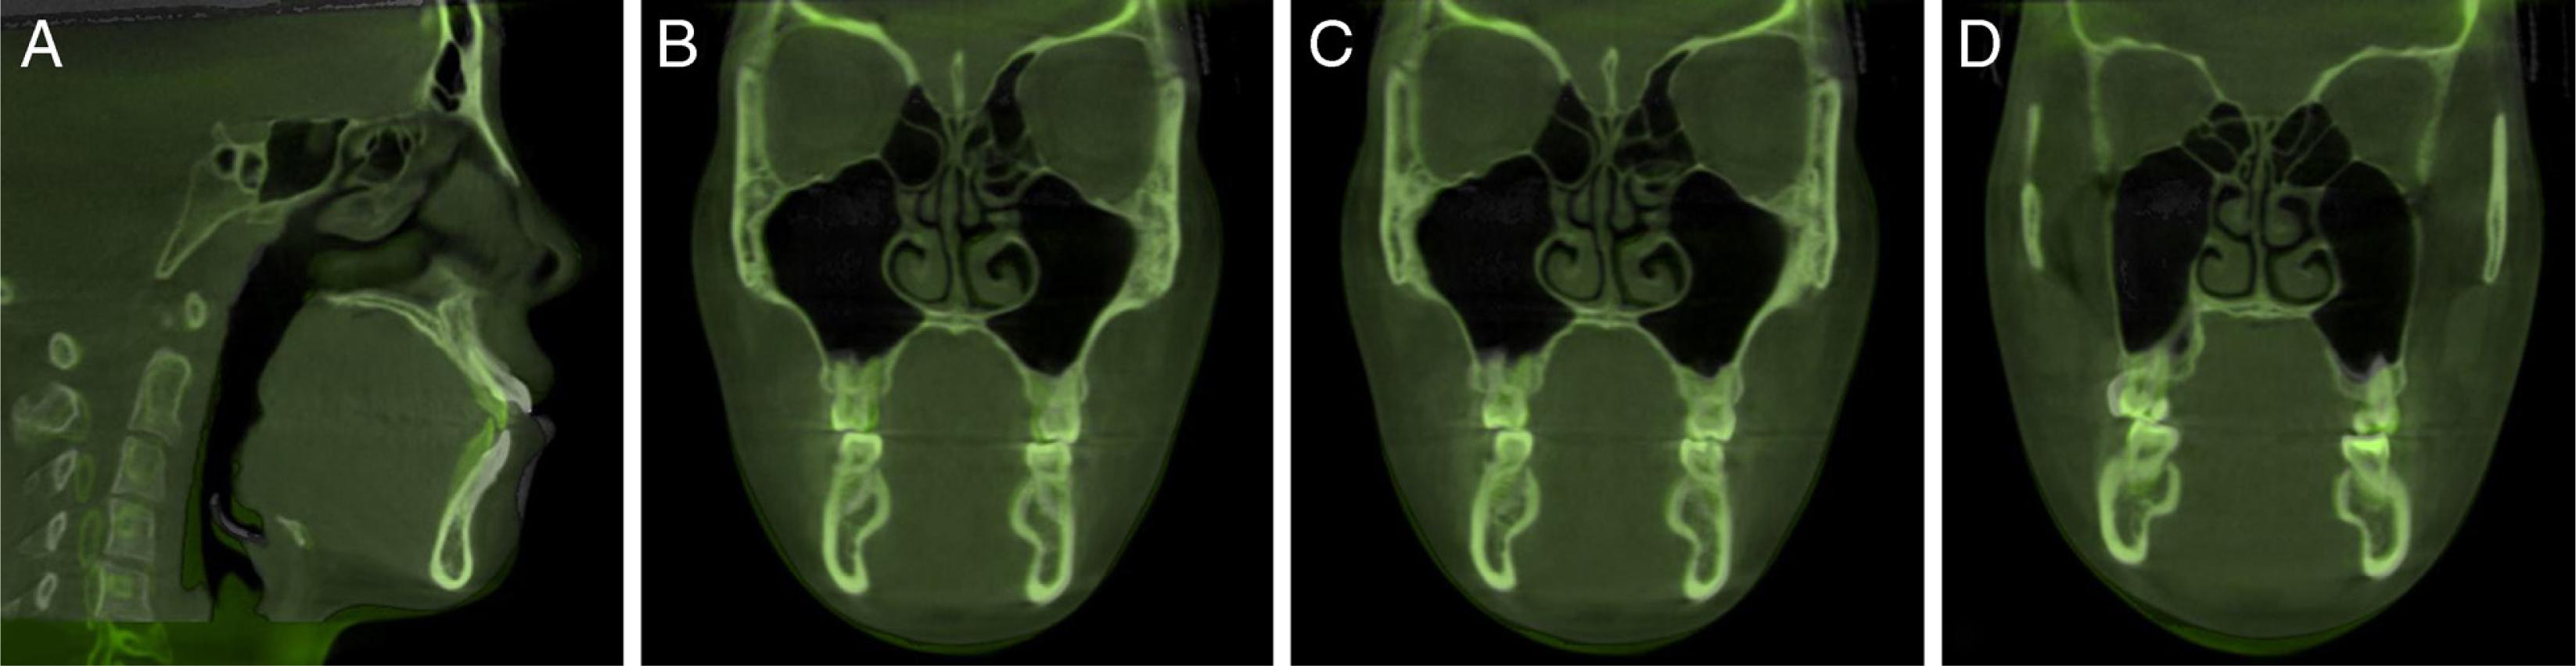

Figure 1.